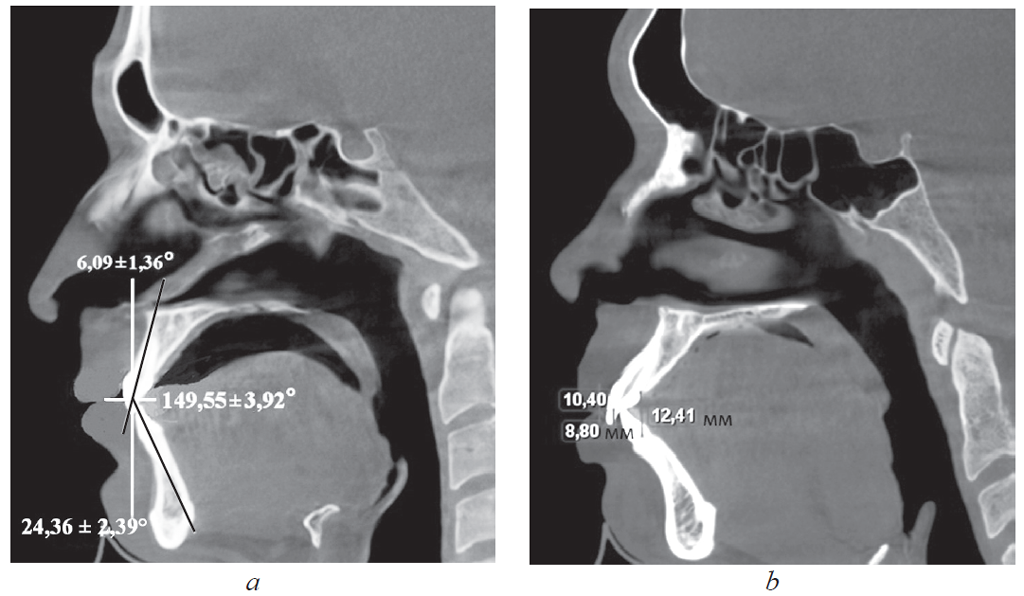

У людей 1-й подгруппы, для которых было характерно протрузионное положение резцов, межрезцовый угол составил 117,24 ± 2,85°. При этом торковые значения верхних резцов по отношению к окклюзионной плоскости составили 12,24 ± 2,48° (рис. 2).

Рис. 2. Физиологическая протрузия резцов на томограммах

Fig. 2. Physiological protrusion of incisors on tomograms

У людей 2-й подгруппы при ретрузии резцов величина межрезцового угла в среднем составила 151,47 ± 2,94°, торк верхних резцов — 5,85 ± 1,42°. При этом величина вертикального перекрытия соответствовала величине сагиттального перекрытия и не превышала 2–3 мм.

У людей 1-й подгруппы, для которых было характерно протрузионное положение резцов, межрезцовый угол составил 117,24 ± 2,85°, при этом торковые значения верхних резцов по отношению к окклюзионной плоскости — 12,24 ± 2,48° (рис. 4).

Рис. 4. Патологическая ретрузия (а) и патологическая протрузия (b)

Fig. 4. Pathological retrusion (a) and pathological protrusion (b)

У пациентов с ретрузией резцов отмечалось увеличение межрезцового угла и уменьшение торковых значений резцов, так же как и при физиологической ретрузии. Однако величина перекрытия существенно отличалась от аналогичных показателей, полученных у пациентов I группы. При этом наблюдалось несоответствие размеров вертикального и сагиттального перекрытия.